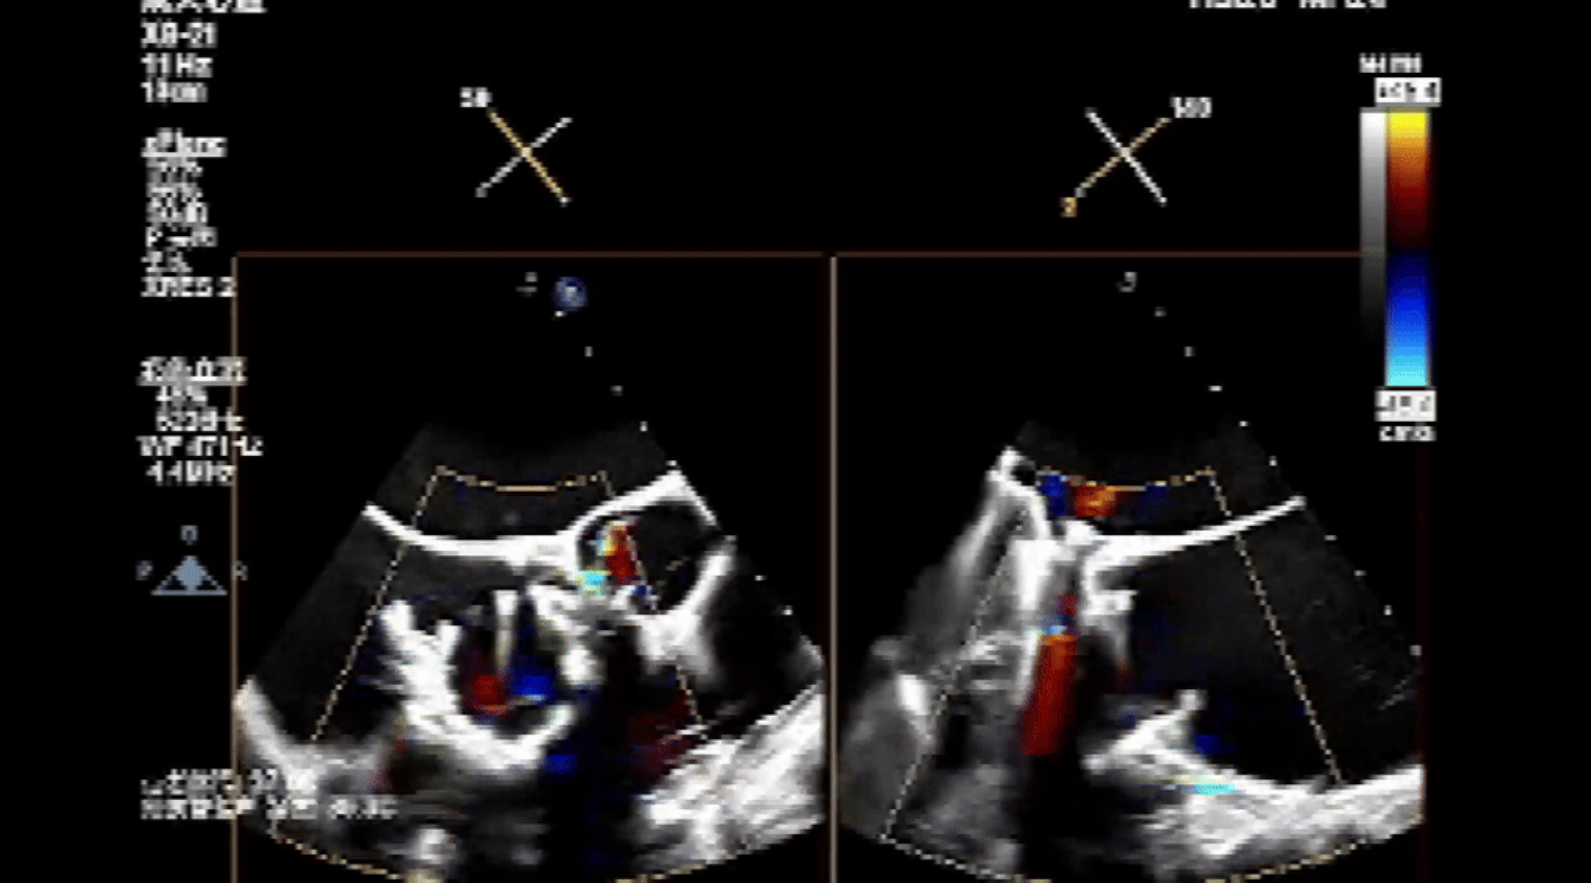

術(shù)前心臟超聲提示:三尖瓣大量返流,右心房容積明顯增大,三尖瓣瓣環(huán)顯著擴(kuò)張。

術(shù)后心臟超聲提示:Lux-Valve Plus植入術(shù)后,三尖瓣瓣環(huán)處可見人工瓣膜回聲,未見返流,人工瓣膜穩(wěn)定,瓣葉開閉良好,連續(xù)多普勒估測三尖瓣平均跨瓣壓差僅為1mmHg。